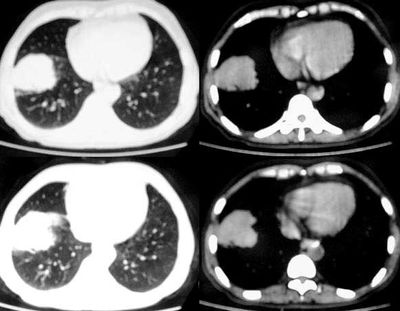

球形肺炎是大叶性肺炎的一种特殊表现[1],以肺的渗出实变为主。它的机理未明,可能是由于抗生素的广泛应用,大叶性或节段性肺炎发展受到限制而形成球形,其形成又与病缘菌的毒性数量及机体的免疫能力有关。病人多有感然症状,某些病人无明显感然症状。病变呈球形或椭圆形,大小不等,病灶密度多均匀,ct值稍低于软组织密度;或中央密度高,边缘密度低,显示晕圈状改变;有时可见空洞[2]。病灶边缘比较规则,也可不规则,有毛刺或呈锯齿状改变,但较模糊。位于肺周区,贴近胸膜,部分病栽表现为两侧缘垂直于胸膜,呈刀切样平直边缘。病灶周围血管纹理增多、增粗、常有局限性胸膜增厚。球形肺炎抗炎两周后,病灶即有缩小,最后能完全吸收。

球形肺炎:病变密度相对较淡,中央密度略高,ct图片上密度较为均匀,增强中央可出现无强化区。病变邻近胸膜反应较为显著,可表现为增厚、粘连(可以比较广泛),病变内可以见到大血管的贯穿,周围及近肺门侧可以见到血管纹理增多、增粗,可有支气管充气征象,两侧可垂直于胸膜或呈方形,边缘可为刀切征,它可以出现毛刺样的类似改变,短期内抗炎治疗有效。